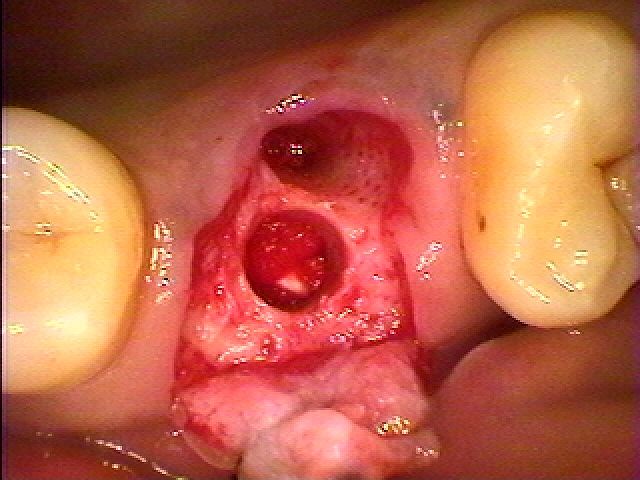

ソケットリフトテクニックにて持ち上げています

ソケットリフトテクニックにて持ち上げています